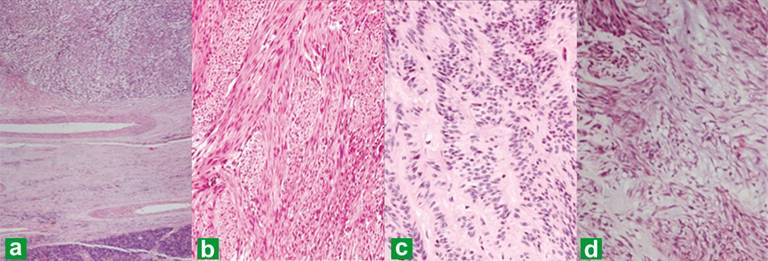

Immunohistochemical Characteristics (Table 4, Figures 4ab)

Immunohistochemistry findings in pEGISTs closely resembled those of resident pancreatic interstitial cells of Cajal as described by Popescu et al. [25] and GISTs arising from other anatomic sites. Sixteen of 19 (84.2%) pEGISTs showed strong diffuse cytoplasmic positivity for CD117/c-KIT, and 14/19 (73.7%) were positive for CD34, thus making these two as most sensitive marker at this site. The tumor cells were consistently negative for S-100 (12/12), α-smooth muscle actin (SMA, 11/11), desmin (7/7), cytokeratin (6/6), and chromogranin (2/2), a feature in contrast to other studies [15, 57, 58]. Babu et al. [47] recently described a case of DOG-1 positive pEGIST. Krska et al. [31] described a case of pEGIST which showed positivity for synaptophysin and gastrointestinal autonomic nerve cell tumor (GANT) like features in transmission electron microscopy studies. Positivity for neuronal markers like neuron specific enolase has been reported from GISTs involving different anatomic sites [15, 58].

Figures 4. Immunohistochemical staining of tumor cells with c-KIT/CD117 (a.) and CD34 (b.) showing strong cytoplasmic positivity. The tumor cells were consistently negative for S-100 and α- smooth muscle actin (SMA). (Original magnification, 100x). |